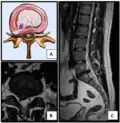

The majority of disc herniations occur in the lumbar spine (95% at L4–L5 or L5–S1).[21] The second most common site is the cervical region (C5–C6, C6–C7). The thoracic region accounts for only 1–2% of cases. Herniations usually occur postero-laterally, at the points where the annulus fibrosus is relatively thin and is not reinforced by the posterior or anterior longitudinal ligament.[21] In the cervical spine, a symptomatic postero-lateral herniation between two vertebrae will impinge on the nerve which exits the spinal canal between those two vertebrae on that side.[21] So, for example, a right postero-lateral herniation of the disc between vertebrae C5 and C6 will impinge on the right C6 spinal nerve. The rest of the spinal cord, however, is oriented differently, so a symptomatic postero-lateral herniation between two vertebrae will impinge on the nerve exiting at the next intervertebral level down.[21]

Herniated lumbar disc

Lumbar disc herniations occur in the back, most often between the fourth and fifth lumbar vertebral bodies or between the fifth and the sacrum. Here, symptoms can be felt in the lower back, buttocks, thigh, anal/genital region (via the perineal nerve), and may radiate into the foot and/or toe. The sciatic nerve is the most commonly affected nerve, causing symptoms of sciatica. The femoral nerve can also be affected and cause the patient to experience a numb, tingling feeling throughout one or both legs and even feet or a burning feeling in the hips and legs.[22] A herniation in the lumbar region often compresses the nerve root exiting at the level below the disc. Thus, a herniation of the L4–5 disc compresses the L5 nerve root, only if the herniation is posterolateral.